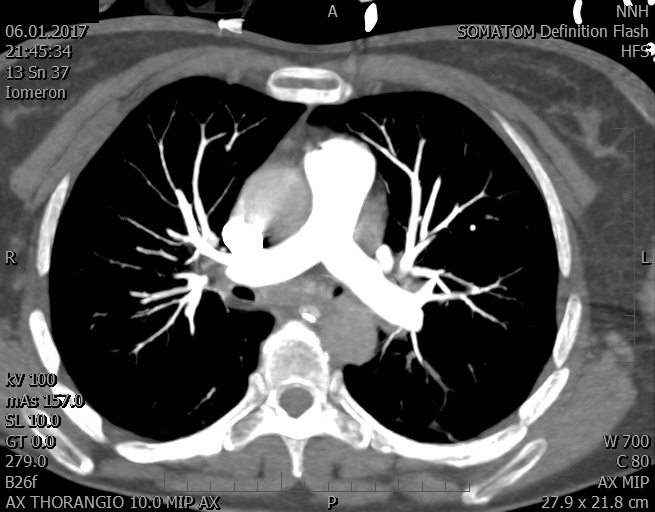

Video 2 - Echokardiograficky byla zjištěna těžká dysfunkce dilatační levé komory s nezvětšenou pravou komorou.Pro nejasnou příčinu zástavy jsme provedli i vyšetření výpočetní tomografií (CT), které vyloučilo plicní embolizaci (série 1 - soubory na konci článku). V den přijetí při přetrvávající oběhové nestabilitě byla nemocná opakovaně defibrilována pro fibrilaci komor se stabilizací rytmu po podání amiodaronu a mesocainu. Dle hemodynamických měření se jednalo o těžký kombinovaný šok. Vstupní laboratorní vyšetření bylo bez větších pozoruhodností. Posléze jsme doplnili anamnézu od příbuzných a zjistili, že pacientka užila do dvou hodin před srdeční zástavou první tabletu amoxicilinu na lehký respirační infekt. Při nevýtěžnosti vstupních vyšetření a nových anamnestických informacích jsme doplnili 14 hodin po kolapsu vyšetření koncentrace tryptázy v séru, která byla extrémně zvýšena (tabulka 2), což nás vedlo k podezření na anafylaxi.